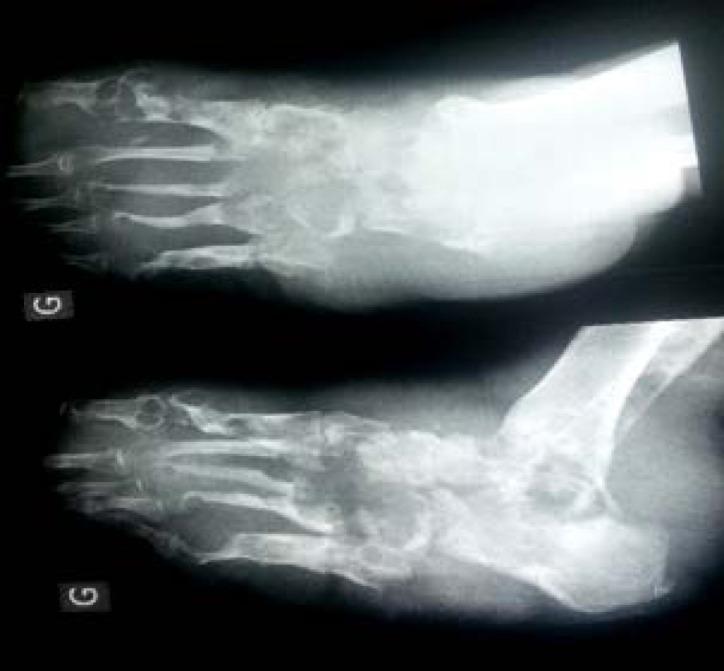

Patients represented 2.3% of hospitalizations and consisted of 11 males and 8 females with an average age of 38 years with extremes of 15 - 70 years, and an average time between the onset of symptoms and presentation to the hospital of 10 years (range 1 - 40 years). Eight livestock breeders and seven farmers were concerned, 14 of whom have started the disease after trauma. The foot was involved in 13 patients. Twelve suffered from osteoarticular lesions. Black grains were present in 16 cases attributed to sp. We performed 12 amputations, six carcinological ablation to which specific local treatments were added (thin skin graft in two patients, fasciocutaneous flap in one patient and directed healing in the others) and local treatment in the last case.

患者占住院患者的2.3%,包括11名男性和8名女性,平均年龄38岁,年龄范围为15至70岁,症状出现至入院的平均时间为10年(范围1至40年)。涉及8名畜牧养殖者和7名农民,其中14人在创伤后发病。13名患者足部受累。12人患有骨关节病变。16例出现黑色颗粒,归因于 菌。我们进行了12次截肢手术,6次肿瘤切除并辅以特定局部治疗(2例患者进行薄皮移植,1例患者进行筋膜皮瓣移植,其他患者进行直接愈合),最后1例进行局部治疗。